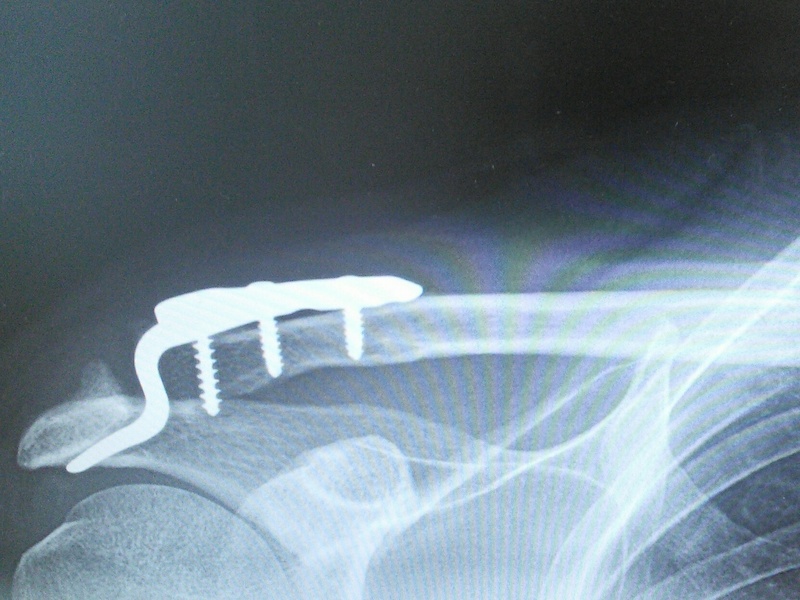

Korjaus onnistunut ainakin eilisen kuvan perusteella.Toipuminen on ollut parasta A-ryhmää.

Tässähän intoutuu speksailemaan jotain uutta maasturia ensi keväälle.Mä luulen että silloin händy kestää ajella normisti.